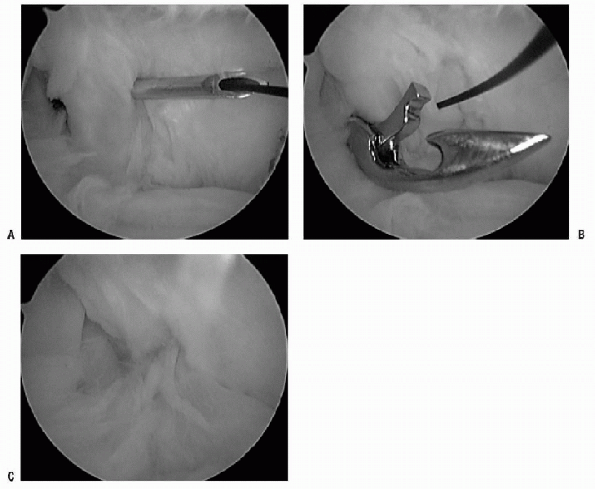

Many authors have reported techniques on

interval closure involves removing the anterior-inferior cannula and

placing all instrumentation through the anterior-superior cannula. The

medial glenohumeral ligament and/or a small portion of the

subscapularis tendon is pierced with either a spinal needle or suture

shuttling device, and a monofilament suture is deployed (Fig. 17-17A). The SGHL/CHL complex is pierced with a penetrator and grasps the monofilament suture (Fig. 17-17B). This tissue then can be tied through a cannula internally or externally and cut with a guillotine knot cutter (Fig. 17-17C). -

Figure 17-17 A: Suture shuttling device through the middle glenohumeral placing a monofilament suture into joint. B: Tissue penetrator through superior glenohumeral ligament and coracohumeral ligament retrieving monofilament suture. C: The rotator interval is closed extra-articularly.